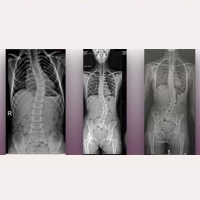

Positiver postoperativer Verlauf einer pädiatrischen Patientin mit idiopathischer Skoliose, vier Jahre nach Anwendung des Filum System® – Fall 14236 Mehr lesen » 09 Januar, 2026